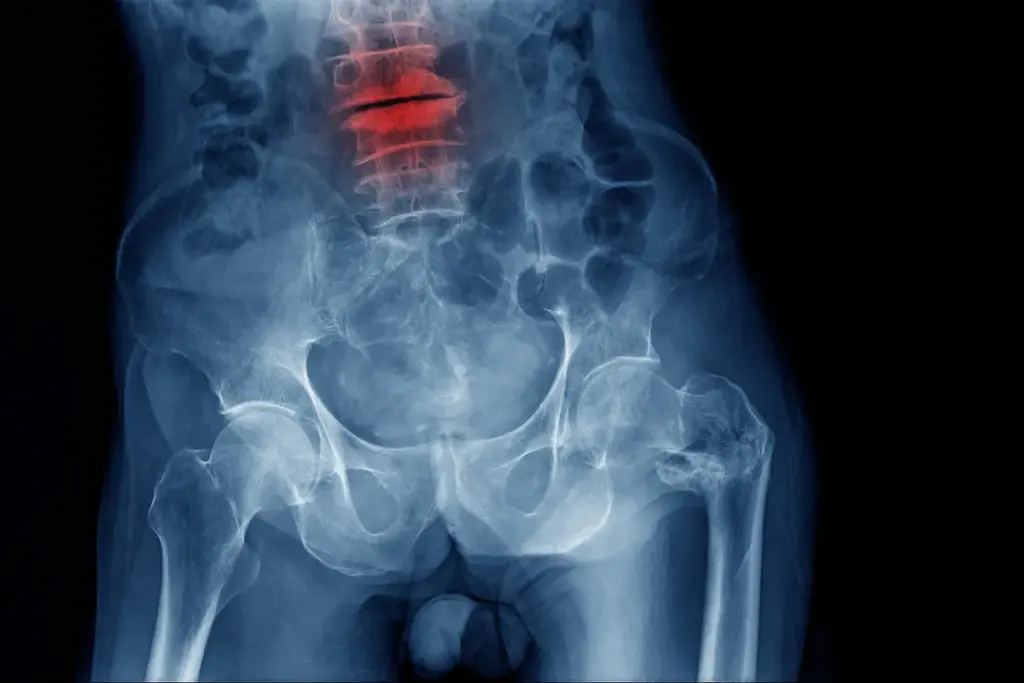

Imaging Technologies (MRI, CT, X-rays)

Imaging is very important for diagnosing. We use MRI, CT scans, and X-rays to see the spine. These tools help us spot disc problems and other issues.

Initial assessment of spinal alignment and disc height |

Useful for initial evaluation and monitoring disease progression |